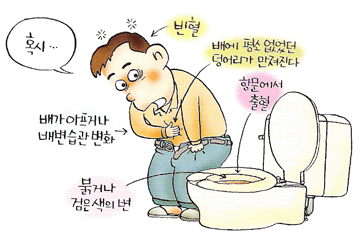

한때 미국 등 서구에서나 발병하는 질환으로 알던 대장암이 우리도 선진국으로 진입하고 식습관은 곡류에서 육류로 급속히 패턴이 바뀌면서 대장질환이 급속히 증가하는 추세이다. 한국중앙암등록본부가 최근 발표한 2011년 국가암등록사업 자료에 의하면 2009년 1년 동안 새롭게 암으로 진단받은 암발생자는 19만2561명 (남 9만9224명, 여 9만3337명)으로 2008년도 18만465명에 비해 6.7% 늘었다. 세계보건기구(WHO) 산호 국제암연구소가 세계 184개국을 대상으로 조사한 세계 대장암 발병현황에 따르면 한국 남성의 대장암 발병률은 10만 명당 46.92명으로 슬로바키아(60.62명), 헝가리(56.39), 체코(54.39)에 이어 세계 4위, 아시아국 1위를 차지했고,여성의 경우도 10만 명당 25.64명으로 젠 세계 184개국 중 19번째를 차지하였다. 암종별로 남자는 위암, 대장암, 폐암, 간암 순이었고, 여자는 갑상선암, 유방암, 대장암, 위암 순으로 많이 발생했으며, 여성에서 처음으로 대장암이 위암을 앞질렀다. 이 때문에 40대 이상이라면 정기적으로 내시경 검사를 받는 것이 좋다. 대장암의 원인 대장암은 음식문화와 생활습관이 직접적으로 연관되는 대표적인 암이다. 과거에 비해 발생률이 증가한 가장 큰 이유는 식습관의 변화 즉, 식생활의 서구화다. 식물성 섬유소 섭취는 감소하고 동물성지방과 단백질 섭취는 증가하는 육류 위주의 식생활이 문제다. 육류와 햄버거, 감자튀김 등 인스턴트 식품 섭취 증가가 주원인으로 꼽힌다. 더 구체적으로 표현하면 과다한 육류 섭취 및 고지방식 때문이다. 동물성 지방을 많이 섭취하면 간에서 콜레스테롤과 담즙산의 분비가 증가된다. 콜레스테롤은 대사 과정에서 발암물질을 만들며, 담즙산은 대장 세포를 손상시킨다. 섬유질 섭취가 부족한 것도 문제다. 섬유질은 음식물이 장을 통과하는 시간을 단축시킴으로써 발암물질과 장 점막과의 접촉시간을 단축시키고 장 내 발암물질을 희석시키는 작용을 한다. 또한 스트레스 및 불규칙한 생활 습관, 과도한 음주, 흡연도 대장암의 원인이라 할 수 있다. 유전적인 요인도 존재하며, 대장암은 약 10~30%의 환자에게서 가족력을 보인다고 알려져 있다. 대표적으로 스트레스 많이 받는 직장인이 흡연과 함께 잦은 술자리에서 삼겹살에 소주를 마신다면 위험인자에 전면적으로 노출되고 있는 샘이다. 대장용종이란 대장 점막이 비정상적으로 자라 조그만 혹같이 돌출되어 있는 상태를 말한다. 50세 이상인 경우 30-40% 가량에서 대장용종이 발견되고 있으며 대부분 내시경적으로 절제가 가능하다. 조기대장암 치료-내시경적 절제술 한국의 대장암 치료성적은 세계 1위 수준이다. 우리나라 대장암 5년 생존율은 지난 15년 동안 54.8%에서 70.1%로 크게 향상됐다. 이는 미국 65%, 캐나다 61%, 일본 65% 등 의료 선진국보다 훨씬 높은 수치다. 내시경검사를 통한 조기발견과 치료기술이 발달한 결과다. 내시경검사를 하면 마치 장속에 들어가서 직접 눈으로 보는 것 같은 선명한 영상을 얻을 수 있다. 그리고 검사하는 동안 병변이 있으면 즉시 떼어내서 조직검사를 할 수 있다. 병변이 작은 경우는 한 번에 모두 제거할 수도 있다. 만일 종양이 발견되면 조직검사를 통해 현미경으로 진단한다. 점막에 국한된 조기 대장암의 경우에는 내시경적 절제술로 치료가 가능하다. 그러나 내시경적 절제술 후 떼어낸 조직을 면밀히 검토했을 때 일부 추가수술이 필요할 수도 있다. 대장암 치료에 있어 수술적 치료는 가장 근본이 되는 치료이다. 과거에는 20cm의 절개창을 내는 개복술이 주를 이루었으나, 최근에는 복강경을 이용한 수술이 많이 이루어지고 있는 추세이다.

대장암에 안 걸리려면 편식을 하지 않고 음식을 골고루 섭취해야 하며 육류나 패스트푸드보다는 신선한 채소와 과일이 몸에 좋다. 하루 30분 이상 규칙적인 운동을 해야하며 적정한 체중을 유지해야 한다. 모든 병의 근원인 담배를 끊고 과음도 피해야한다. 무엇보다도 정기검진을 통해 용종을 발견하고 제거하는 것이 가장 효과적인 예방법이라고 전문의들은 입을 모은다. 경기도 안산 한사랑병원 최동현 원장은 “대장암의 원인은 환경적 요인과 유전적 요인이 복합되어 발생한다고 알려져 있는데, 대장암 가족력이 있을 경우 그렇지 않은 사람에 비해 대장암 발병율이 2~3배 정도 높다고 알려져 있으므로 신경써서 정기적인 검사를 해보시는 것이 좋다”며 “대장암의 대부분은 선종성 용종에서 비롯된다고 알려져 있기 때문에 조기에 발견하여 제거해버린다면 대장암의 상당부분은 예방할 수 있으므로 40대 이상 중장년층은 정기적으로 내시경검사를 받아야한다”고 조언했다. 유로저널 김태호 기자 eurojournal02@eknews.net